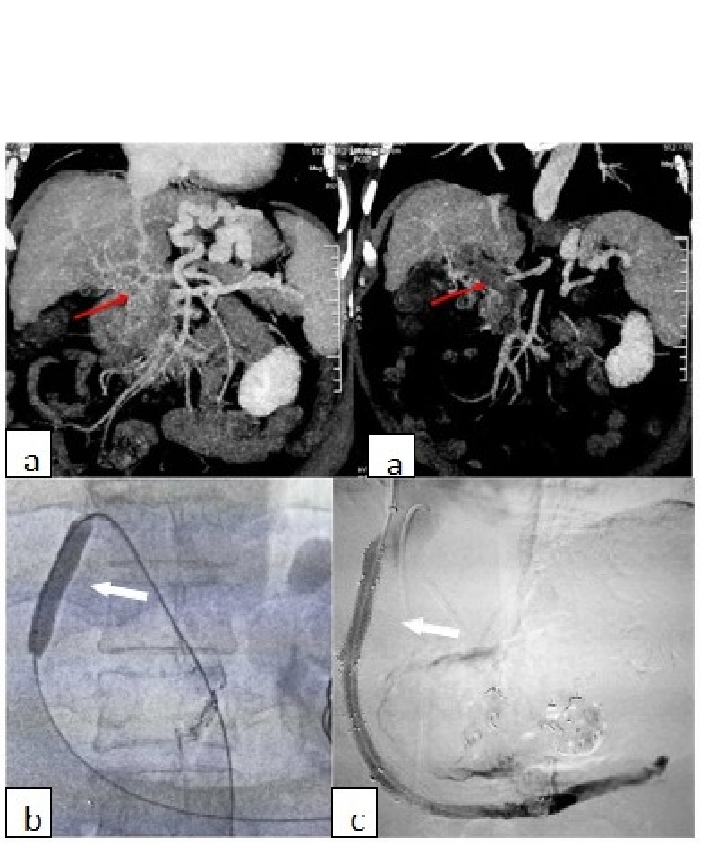

血栓抽吸、扩张后行TIPS(肝硬化基础PVT)

直接TIPS+支架压迫血栓 (肝硬化基础PVT)

与粗大门静脉侧枝行TIPS (肝硬化基础PVT)